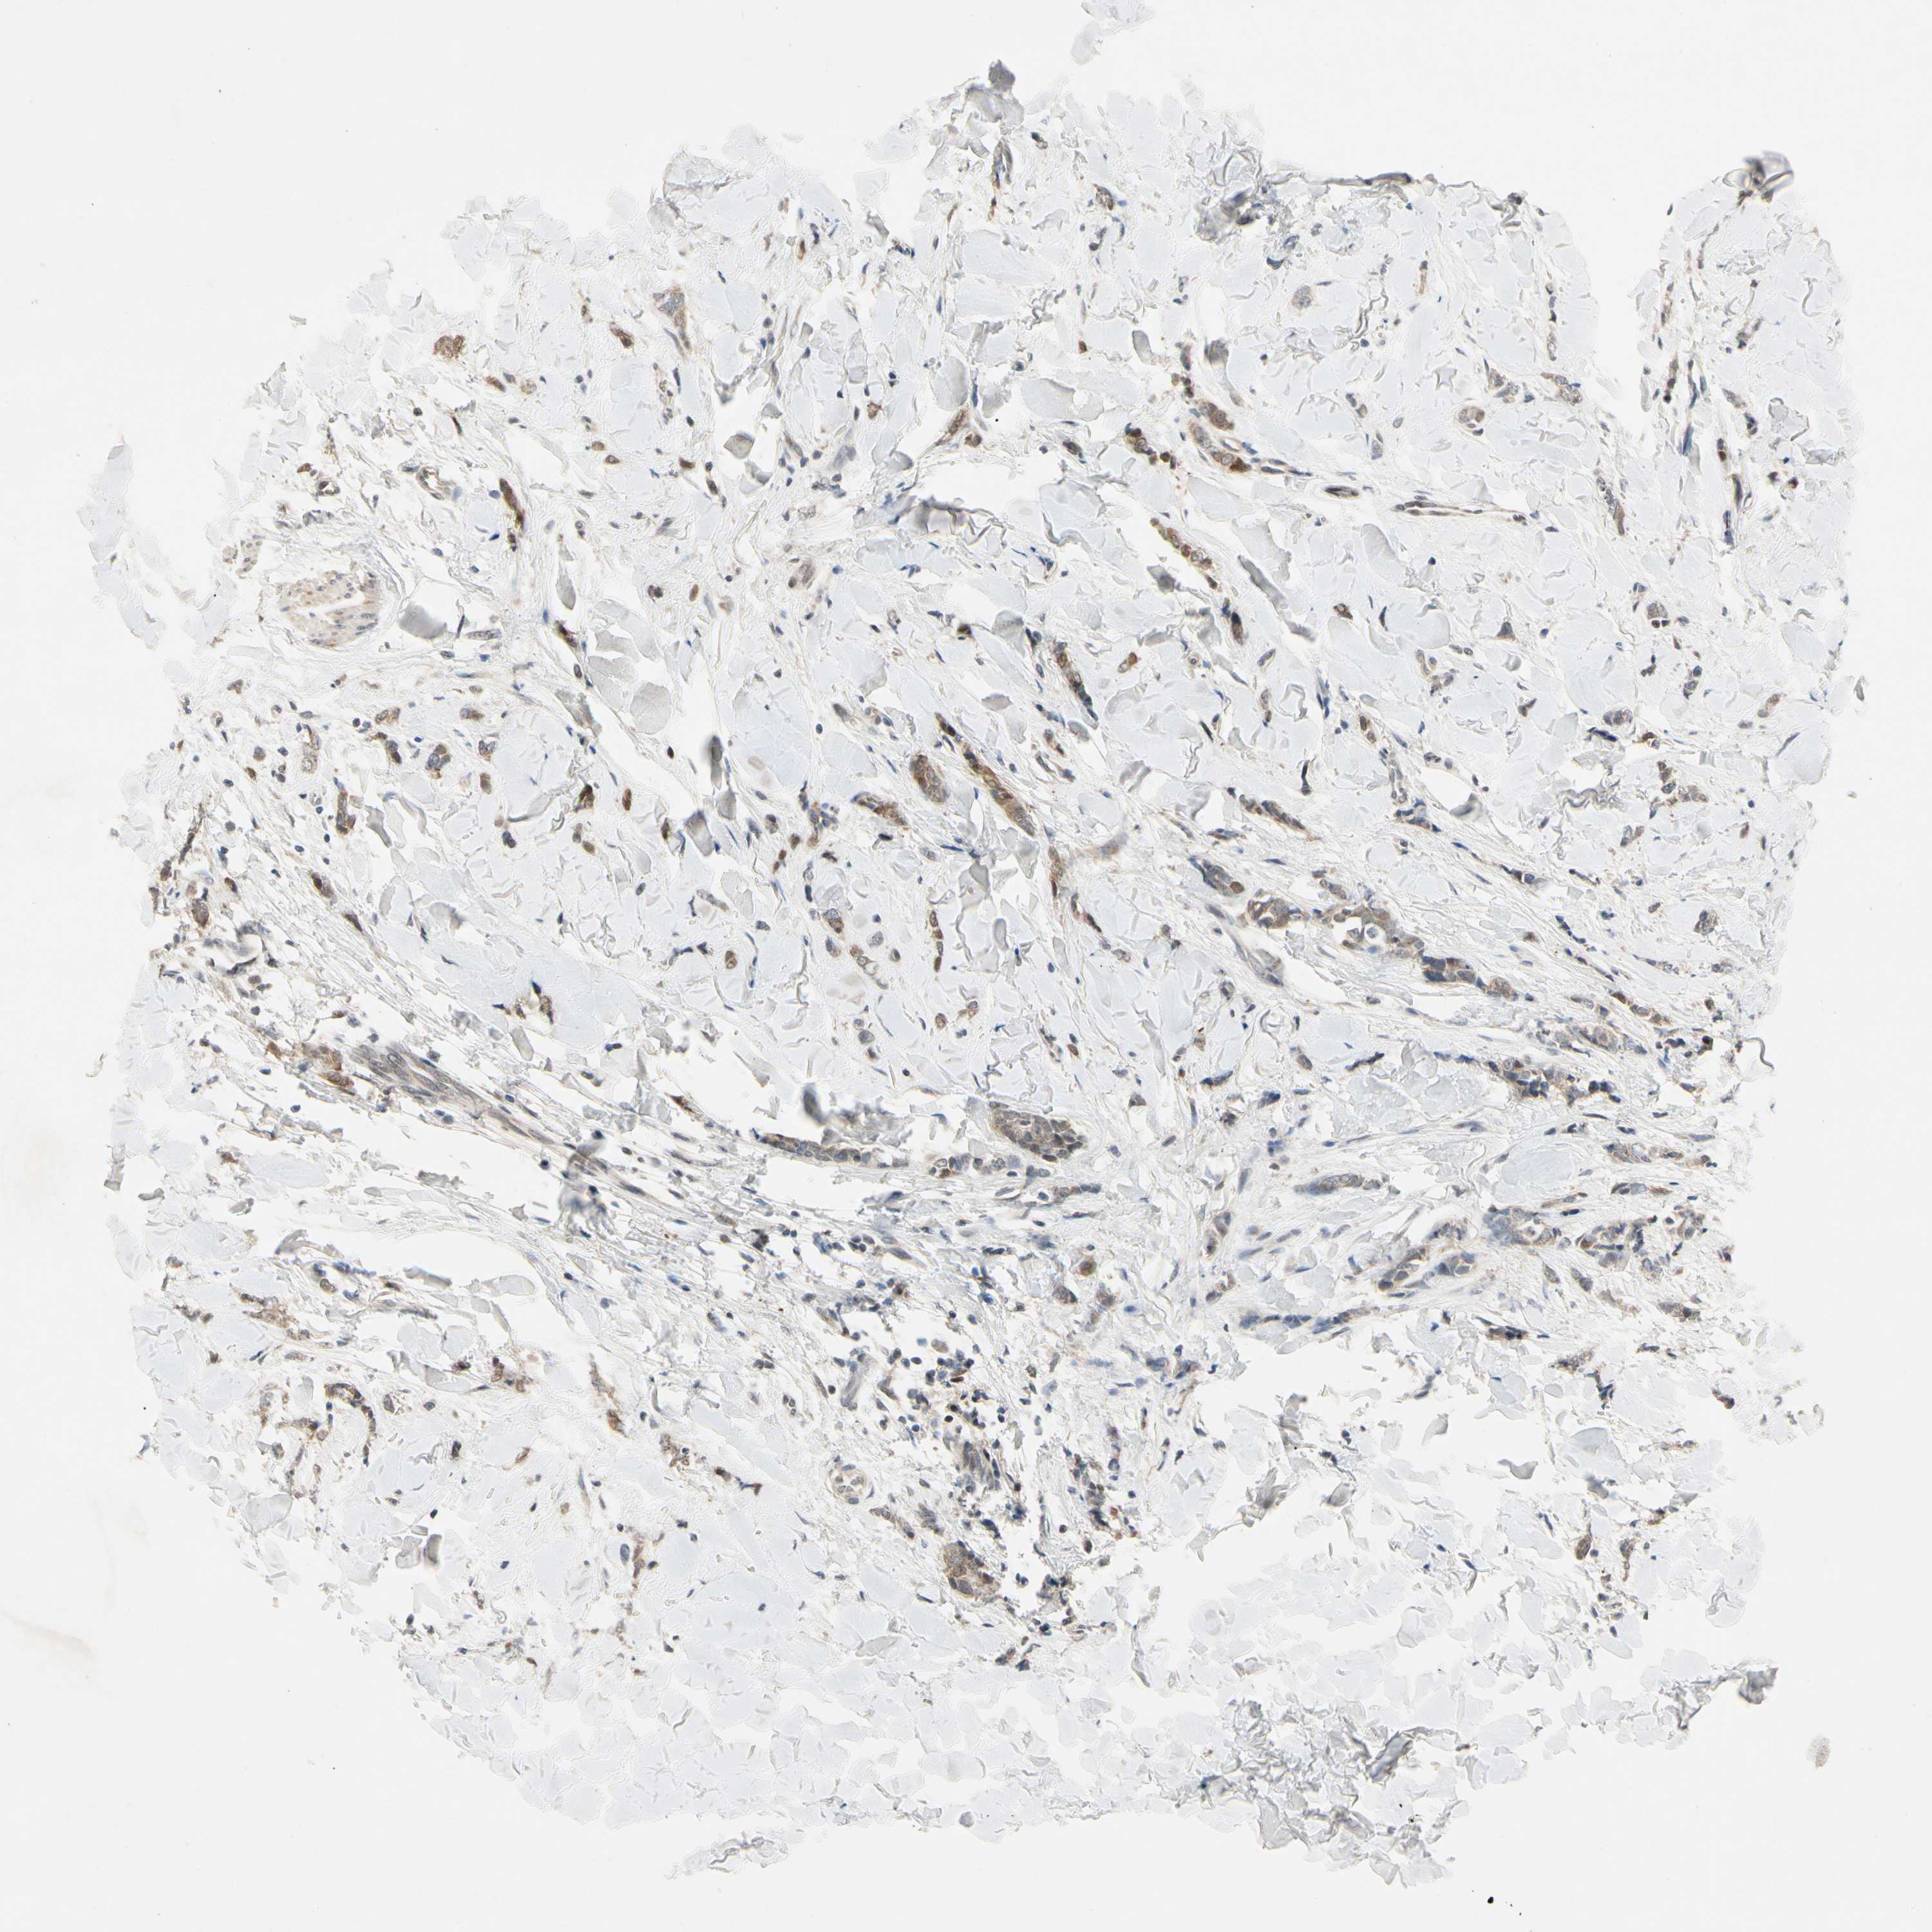

CANCER BREAST CANCER Show tissue menu

BRCA TCGA BRCA VALIDATION PROTEIN EXPRESSION

RIOX2 is potential prognostic, high expression is unfavorable in Breast Invasive Carcinoma (TCGA)